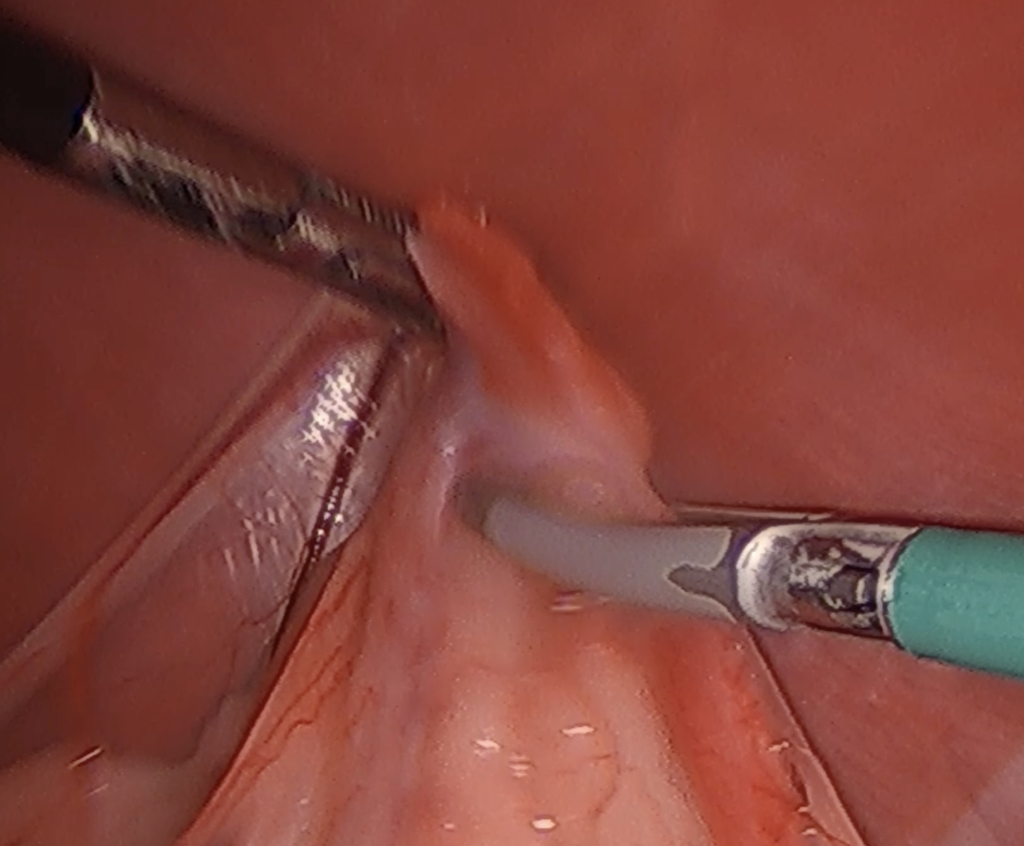

まず腹腔鏡とはお腹に小さな穴を開け、そのカメラを見ながら臓器を観察する医療機器のことです

このカメラ画像を見ながら避妊手術をするのが腹腔鏡下避妊手術となります

④カメラ画像を見ながら左右卵巣の摘出